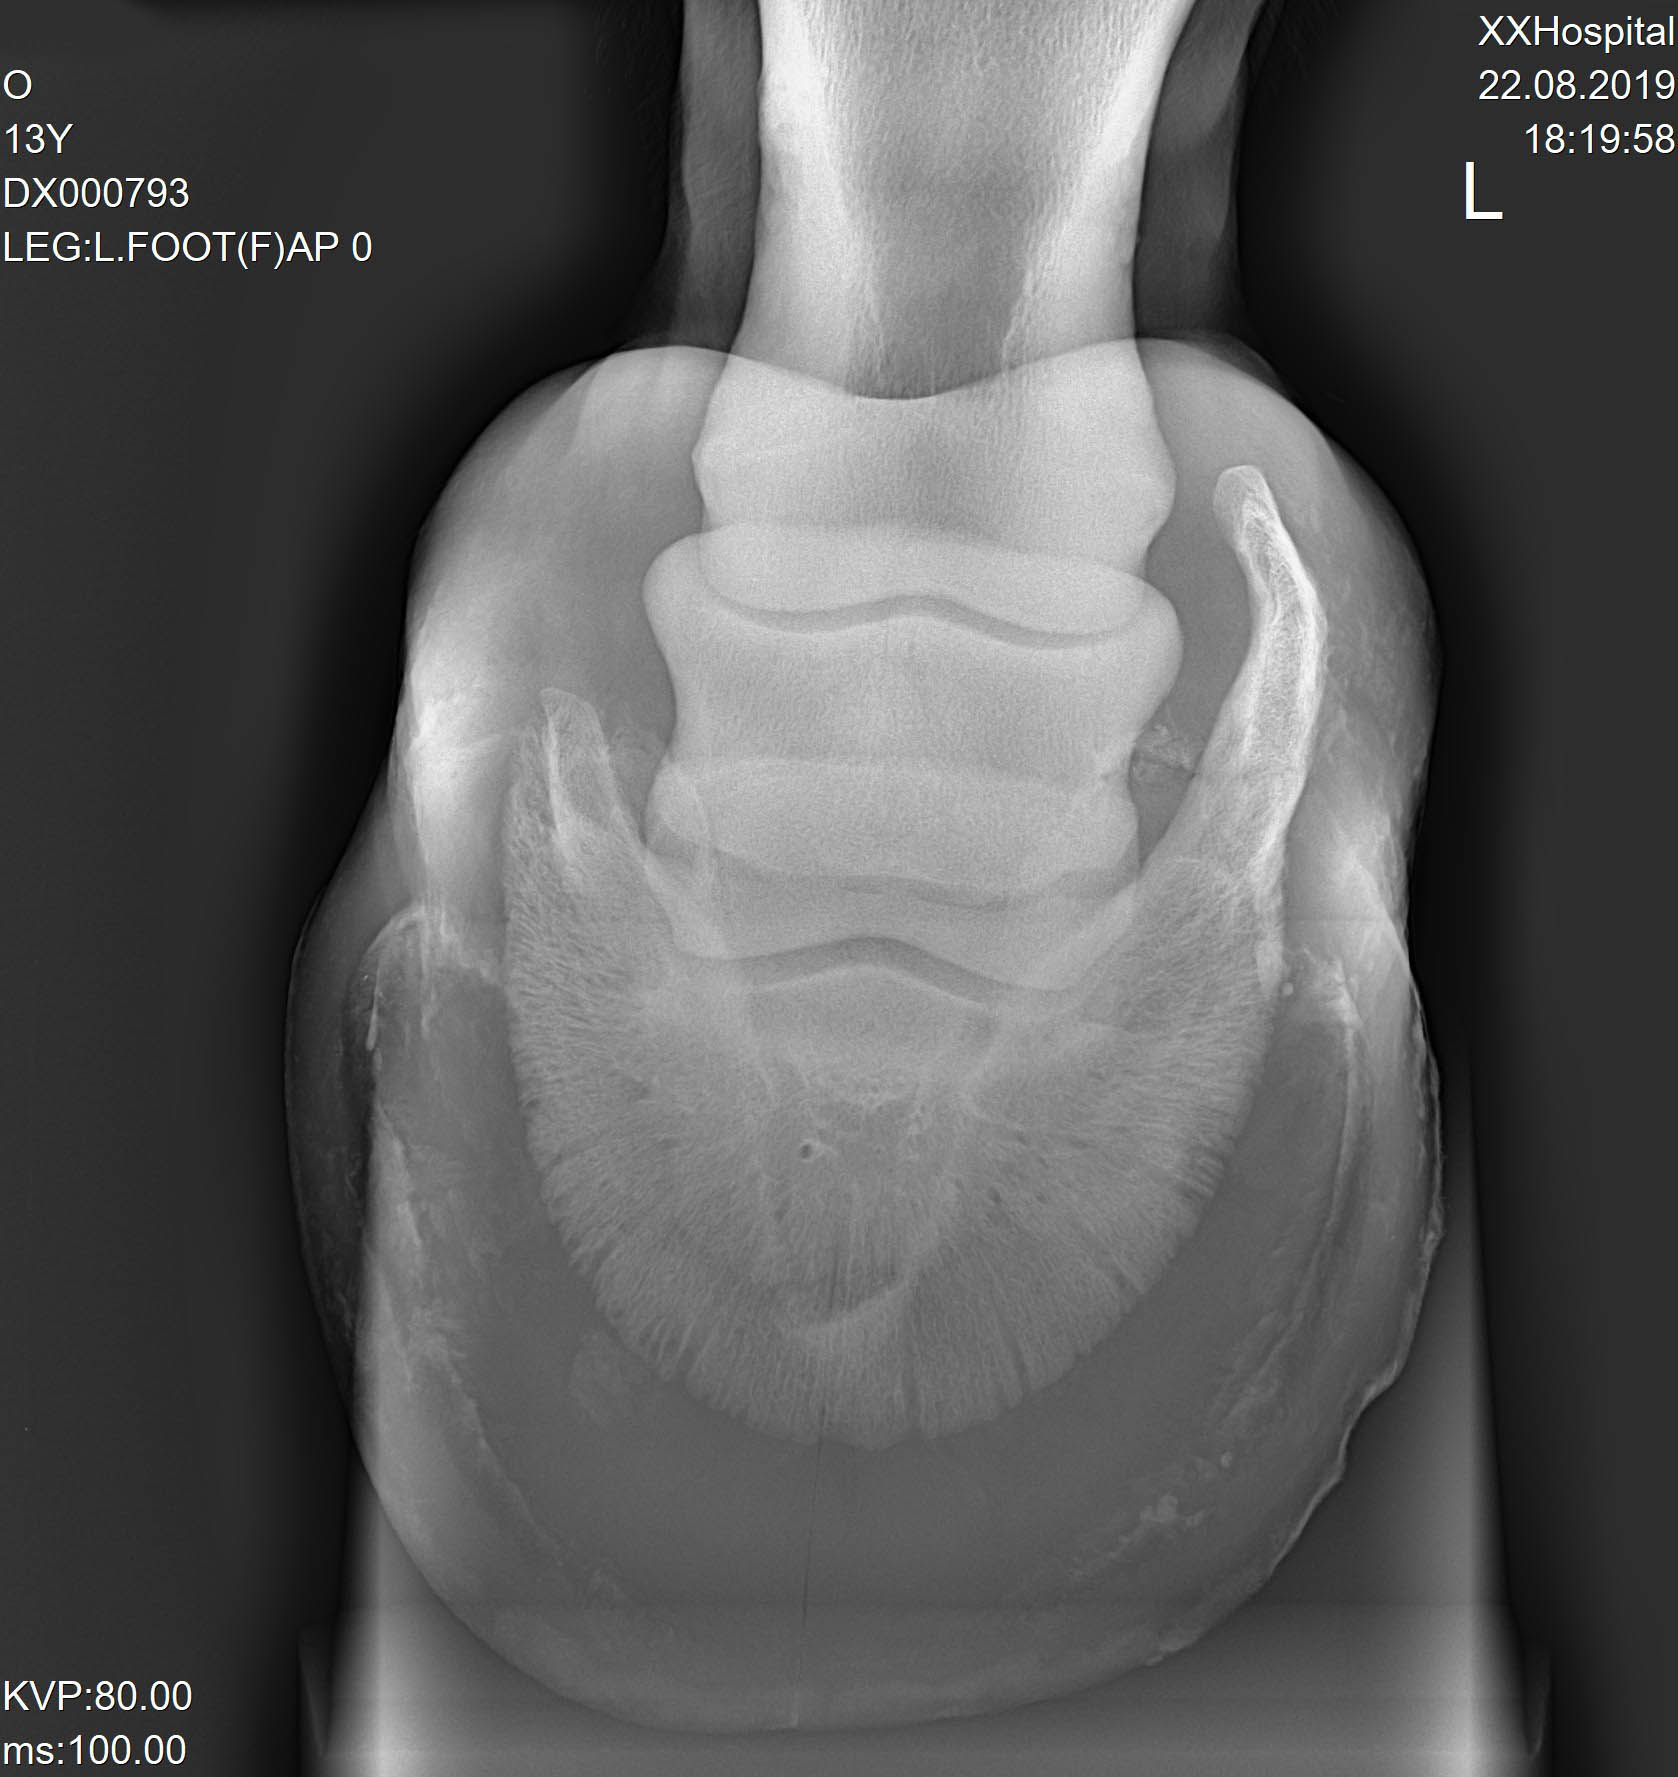

Результаты рентгенологического исследования:

Правая грудная конечность – оссификация латерального хряща копытной кости.

Левая грудная конечность – оссификация латерального хряща копытной кости.